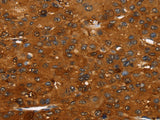

Applications IHC

IHC 1:35-1:150